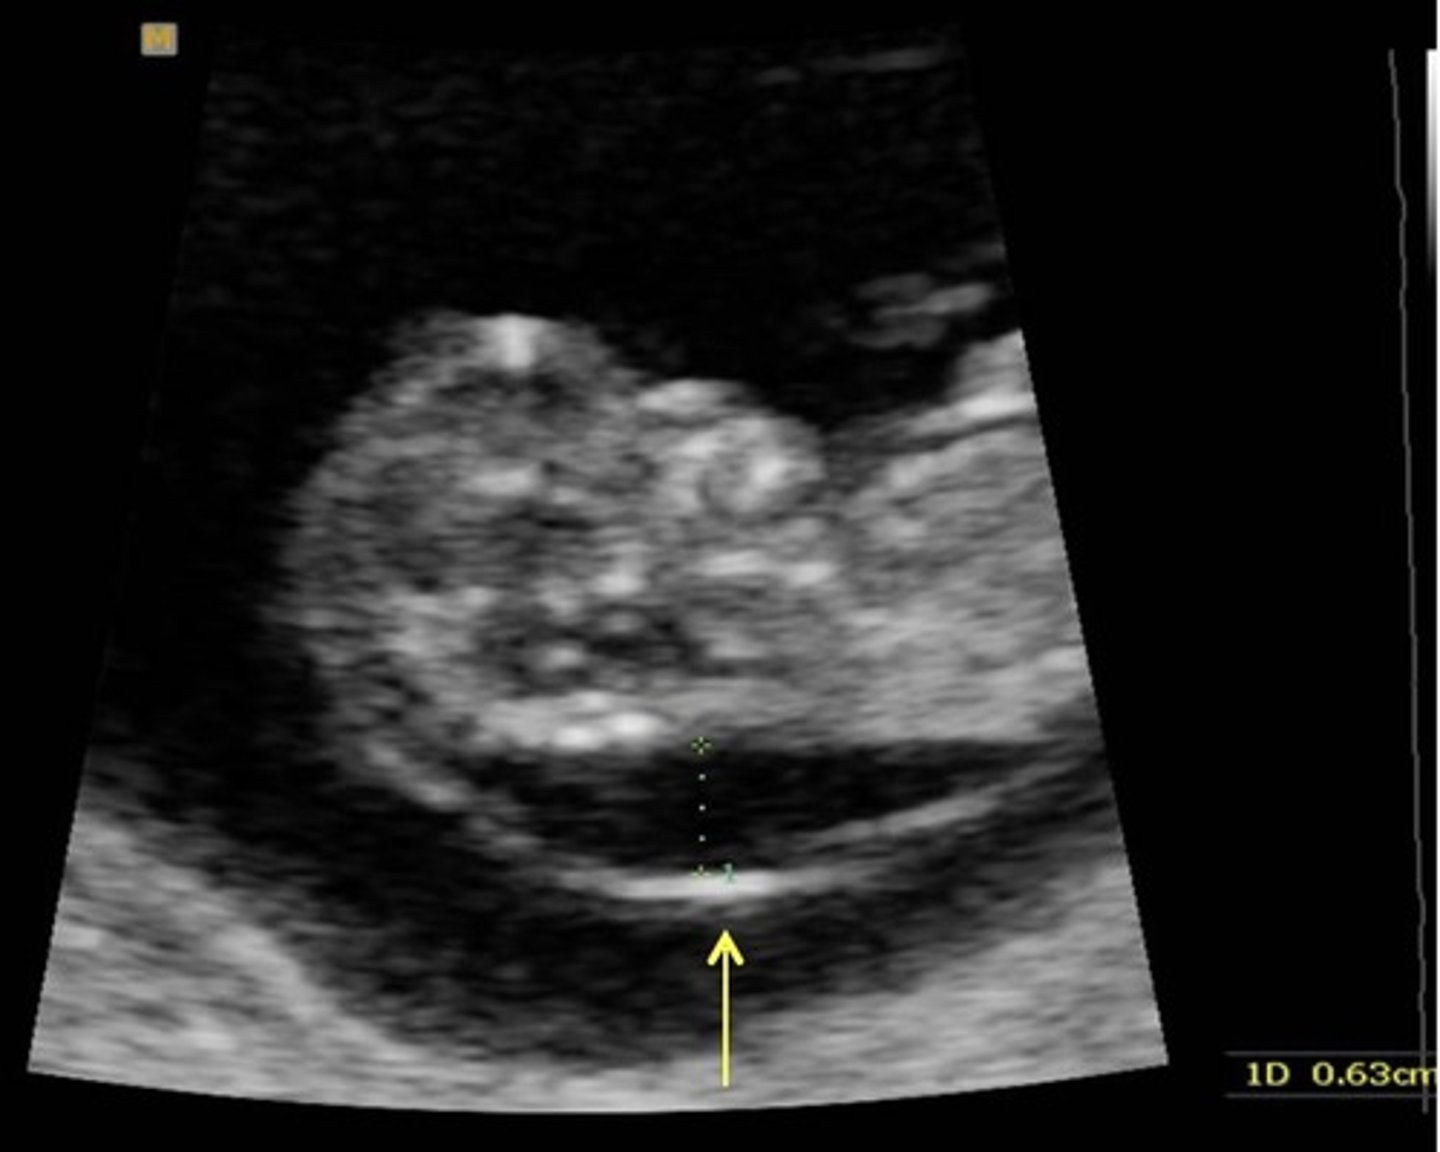

Thickened Nuchal Translucency

Anechoic fluid area in posterior neck region

Associated with Trisomy 21

> 3.4 mm